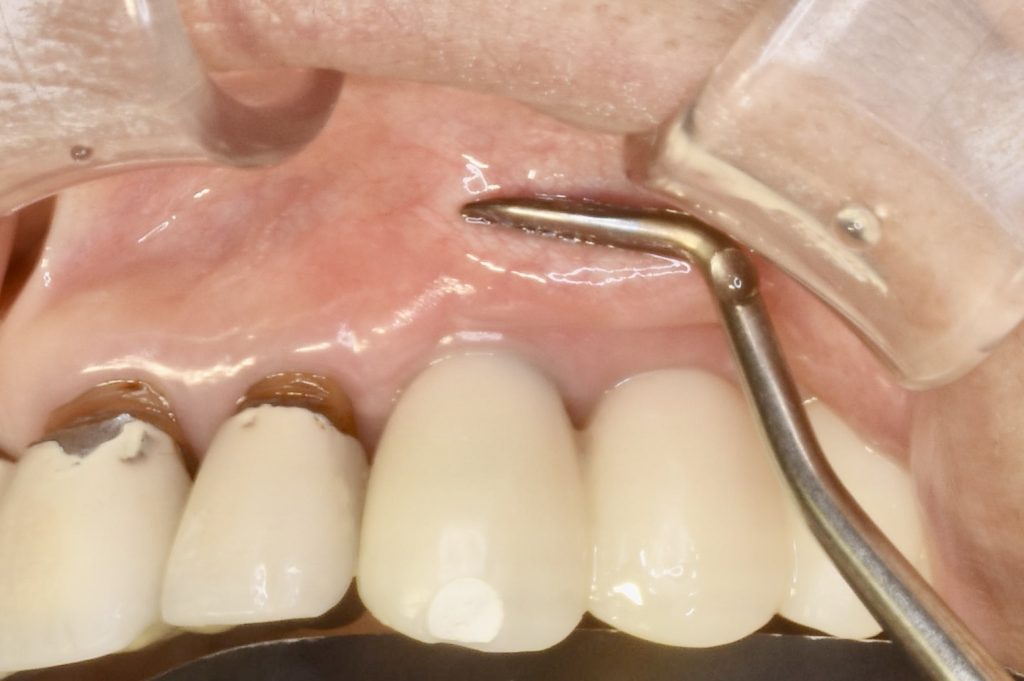

下記の症例は骨幅が薄く、このままでは長期的に安定したインプラント治療が不可能だったので、抜歯と同時に骨造成(GBR)を行い、その後歯肉移植(FGG)を行い、術後安定した経過を辿るよう配慮致しました。